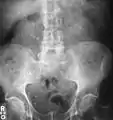

Otherwise a noncontrast helical CT scan with 5 millimeters (0.2 in) sections is the diagnostic method to use to detect kidney stones and confirm the diagnosis of kidney stone disease.[13][47][51][52][7] Near all stones are detectable on CT scans with the exception of those composed of certain drug residues in the urine,[53] such as from indinavir. Calcium-containing stones are relatively radiodense, and they can often be detected by a traditional radiograph of the abdomen that includes the kidneys, ureters, and bladder (KUB film).[53] Some 60% of all renal stones are radiopaque.[51][54] In general, calcium phosphate stones have the greatest density, followed by calcium oxalate and magnesium ammonium phosphate stones. Cystine calculi are only faintly radiodense, while uric acid stones are usually entirely radiolucent.[55]

Where a CT scan is unavailable, an intravenous pyelogram may be performed to help confirm the diagnosis of urolithiasis. This involves intravenous injection of a contrast agent followed by a KUB film. Uroliths present in the kidneys, ureters, or bladder may be better defined by the use of this contrast agent. Stones can also be detected by a retrograde pyelogram, where a similar contrast agent is injected directly into the distal ostium of the ureter (where the ureter terminates as it enters the bladder).[51]

Bilateral kidney stones can be seen on this KUB radiograph. There are phleboliths in the pelvis, which can be misinterpreted as bladder stones.